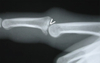

Describe this fracture?

STENER - gamekeeper’s thumb - Avulsion of the ulnar corner of the base of the proximal phalanx of the thumb - Bony equivalent of rupture of the ulnar collateral ligament Thumb spica

107